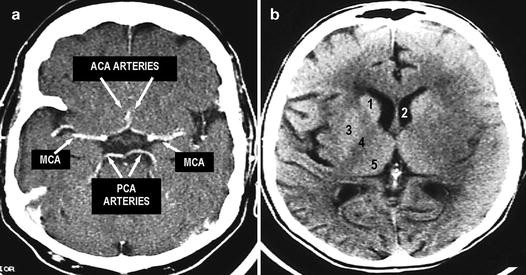

Circle of Willis Challenge Quiz - PurposeGames.com About this Quiz This is an online quiz called Circle of Willis Challenge There is a printable worksheet available for download here so you can take the quiz with pen and paper. From the quiz author Label the circle of willis Your Skills & Rank Total Points 0 Get started! Today's Rank -- 0 Today 's Points One of us! Game Points 15 Illustration of Blood Vessels and Brain Circulation ... Illustration about Illustration of blood vessels and brain circulation, circle of willis with labels. Illustration of brain, flow, willis - 197379708 Non-invasive visualization of collateral blood flow ... The circle of Willis plays an important role in the distribution of blood flow in the brain. To obtain dynamic information of the blood flow through the circle of Willis, a dynamic MRA technique based on arterial spin labeling (ASL) is introduced as a non-invasive technique. When the ASL labeling sl … Penetrating Branches of the Circle of Willis ... Septum Pellucidum Penetrating branches of the Circle of Willis. Coronal section through the brain at the level of the optic chiasm and bifurcation of the internal carotid artery (ICA). On the left side of image, the ICA bifurcates into its two terminal branches, the anterior cerebral artery (ACA) and middle cerebral artery (MCA).

Circle of Willis (COW) - Operative Neurosurgery Circle of Willis (COW) The Circle of Willis (also called Willis' Circle, Loop of Willis, cerebral arterial circle, and Willis Polygon) is the main collateral system between the bilateral carotid systems and the vertebrobasilar system.. Named after Sir Thomas Willis who described the arterial circle (circulus arteriosus cerebri).. The circle of Willis encircles the stalk of the pituitary gland ...